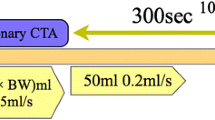

A total of 1.5 ml/kg of bodyweight highly concentrated contrast agent iomeprol (Iomeron 400, Altana) was intravenously administered according to the following protocol: the total amount of contrast minus 30 ml was injected as a bolus (3–4 ml/s), 30 ml were applied over approximately 5 min, starting 60 s after the initial bolus application and running at low rate of 0.1 ml/s. For all CT examinations a standard protocol was used: collimation 64×0.6 mm, gantry rotation time 330 ms, pitch 0.23.

CT examinations were obtained 3, 5, 10 and 15 min after initial contrast application. At 3 and 10 min, a tube voltage of 80 kV along with both the standard 800 mAs for 64-MSCT and a lower tube current of 400 mAs were used. At 5 min, four scans were obtained with all combinations of standard 120 kV and 800 mAs or 80 kV and 400 mAs. The final scan at 15 min was obtained using 80 kV and 800 mAs.